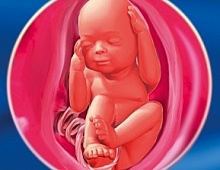

У 24 тижні вага малюка складає 500-600 г, довжина тіла - 29-30 см. На цьому терміні в організмі плода починає синтезуватися гормон росту. Тепер малюк стане набагато активніше додавати у вазі і зростанні, що призведе до швидкого збільшення розмірів живота. Рухова активність плода також буде посилюватися з кожним днем.

Більшу частину внутрішньоутробного існування малюк спить. На частку сну доводиться 16-20 годин на добу. Весь інший час дитина вільно переміщається в амніотичної рідини. Сторож Божий малюк заявляє про себе енергійними ворушіннями, які добре сприймаються жінкою на цьому терміні. В середньому майбутня мама може відчути до 10 рухів плода на добу. Ворушіння на цьому терміні відчуваються внизу живота, нижче рівня пупка.